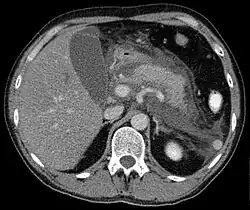

Die erste klare Beschreibung der pathologischen Anatomie der chronischen Pankreatitis stammt von Ch. Dieckhoff (1894).[26] Pankreasverkalkungen werden durch Ultraschall, Röntgenaufnahme des Oberbauches, Computertomografie oder Magnetresonanztomographie nachgewiesen und beweisen eine chronische Pankreatitis. Pankreasgangsteine werden mit der Endoskopisch retrograden Cholangiopankreatikographie bildlich dargestellt.